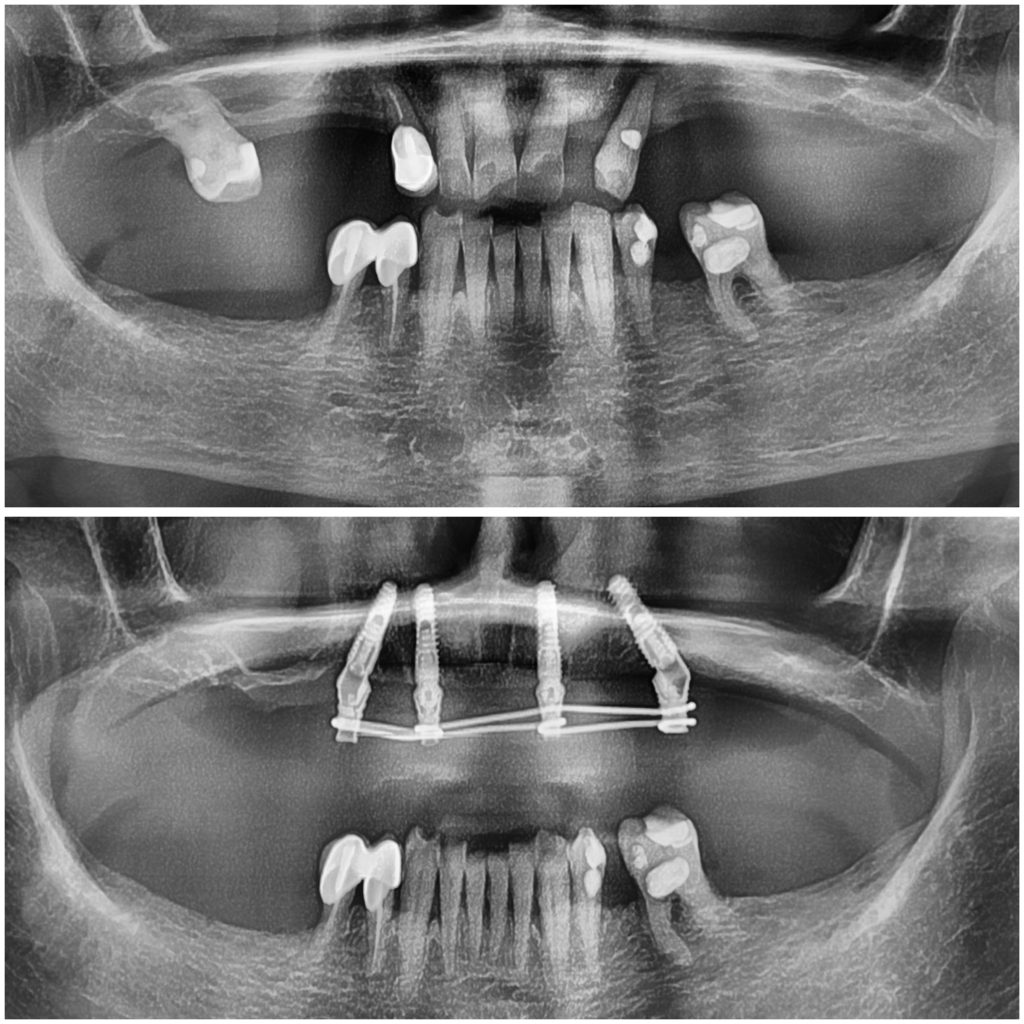

Имплантация All-on-4 в нашей клинике в Москве — это современная методика восстановления всех зубов на одной челюсти с опорой всего на четыре импланта. Технология позволяет получить несъёмные зубы даже при полном отсутствии зубов и выраженной атрофии костной ткани.

Два импланта устанавливаются вертикально, а два — под углом. Такое расположение позволяет максимально использовать имеющуюся кость и часто избежать костной пластики.

Имплантация All-on-4 рекомендуется при:

1. полном отсутствии зубов;

2. разрушенных зубах, не подлежащих восстановлению;

3. выраженной атрофии кости;